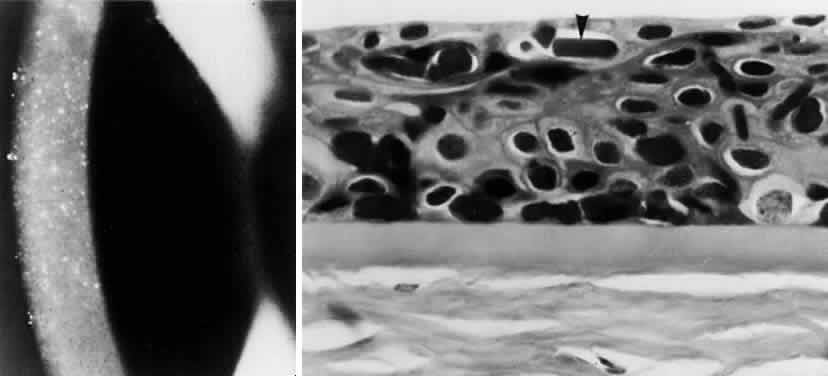

OCULAR FINDINGS. The outstanding clinical feature common to all three phenotypes is the corneal and conjunctival cystine crystal deposition (Figs. 3 and 4). Photophobia is often the only presenting visual symptom; this may be incapacitating and associated with blepharospasm.

Corneal deposits appear as a layer of homogeneously distributed, fusiform or needle-shaped, iridescent crystals situated in the stroma beneath the epithelium. In the infantile form, anterior crystal deposition begins early in life (between 6 and 15 months of age) and proceeds posteriorly as the patient ages; deposition advances more rapidly in the periphery. The anterior location of the crystals may be associated with recurrent erosions.33 The depth of the stromal deposition and the density of crystals is always greater peripherally than centrally. More and larger crystals occur in the superficial stroma. No visual impairment occurs at this early stage. By the age of 7 years, most patients have crystals, either within or on the endothelial surface34,35; markedly decreased corneal sensitivity is also present.36 The spherical contrast sensitivity function is significantly lower in infantile cystinosis than in age-matched controls.37